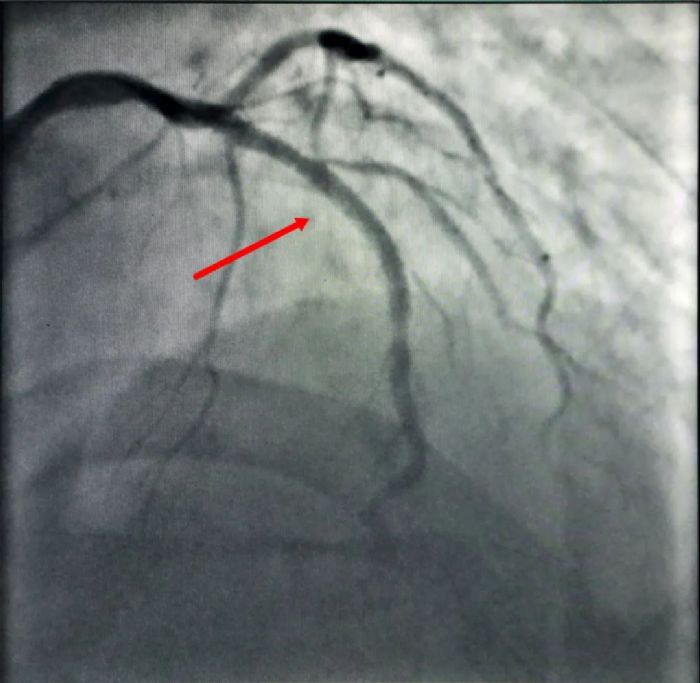

“立即电除颤”“快快快,赶紧心肺复苏”......随着一个个抢救指令不停的从病房内发出,一场与死神的正面“硬刚”随即展开。第一次电除颤很快让吴某恢复了窦性节律和意识,但紧接着,更可怕的情况发生了——心脏“电风暴”来袭,吴某的心脏几次“罢工”,室速、室颤一轮接一轮,险象环生,紧张的气氛弥漫在病房内,尽管汗水早已湿透了衣身,但医护人员仍全力以赴、分秒必争地坚持抢救,在医护人员的默契配合和不懈努力下,经过6次的除颤、心肺复苏后,“电风暴”终于平息下来。 支架植入前(左)和支架植入后(右) 姜同辉主任说:“抢救此类患者,紧急迅速开通血管最为关键!”虽然经除颤、心肺复苏等抢救,吴某的血压、心率得到了改善,但其病情仍未稳定,如再反复发生室颤必将危及生命。姜同辉主任立即将风险及治疗方案告知吴某及家属,征得同意后,迅速将吴某转入介入导管中心行急诊PCI(冠状动脉内支架植入术)治疗。结合病情,经冠脉造影术后,考虑前降支为此次急性心肌梗死“罪犯血管”,立即予吴某前降支植入支架,开通冠脉,改善心肌灌注。50分钟后手术成功,患者转入ICU进一步治疗。由于处置及时,术后吴某各项体征平稳,经一段时间的精心治疗,目前已康复出院。